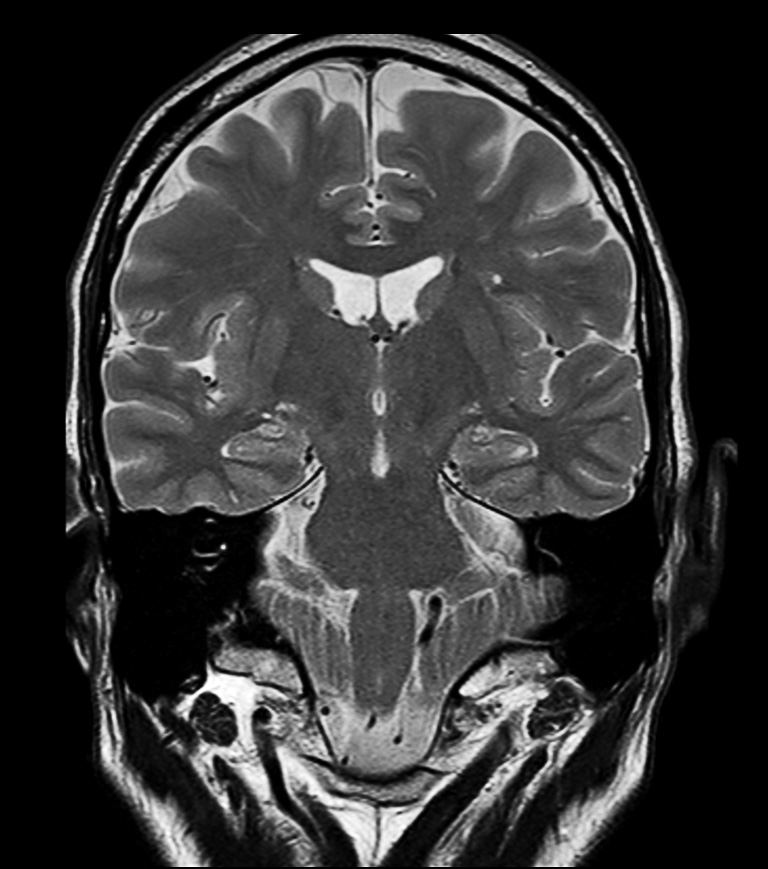

Hippocampus